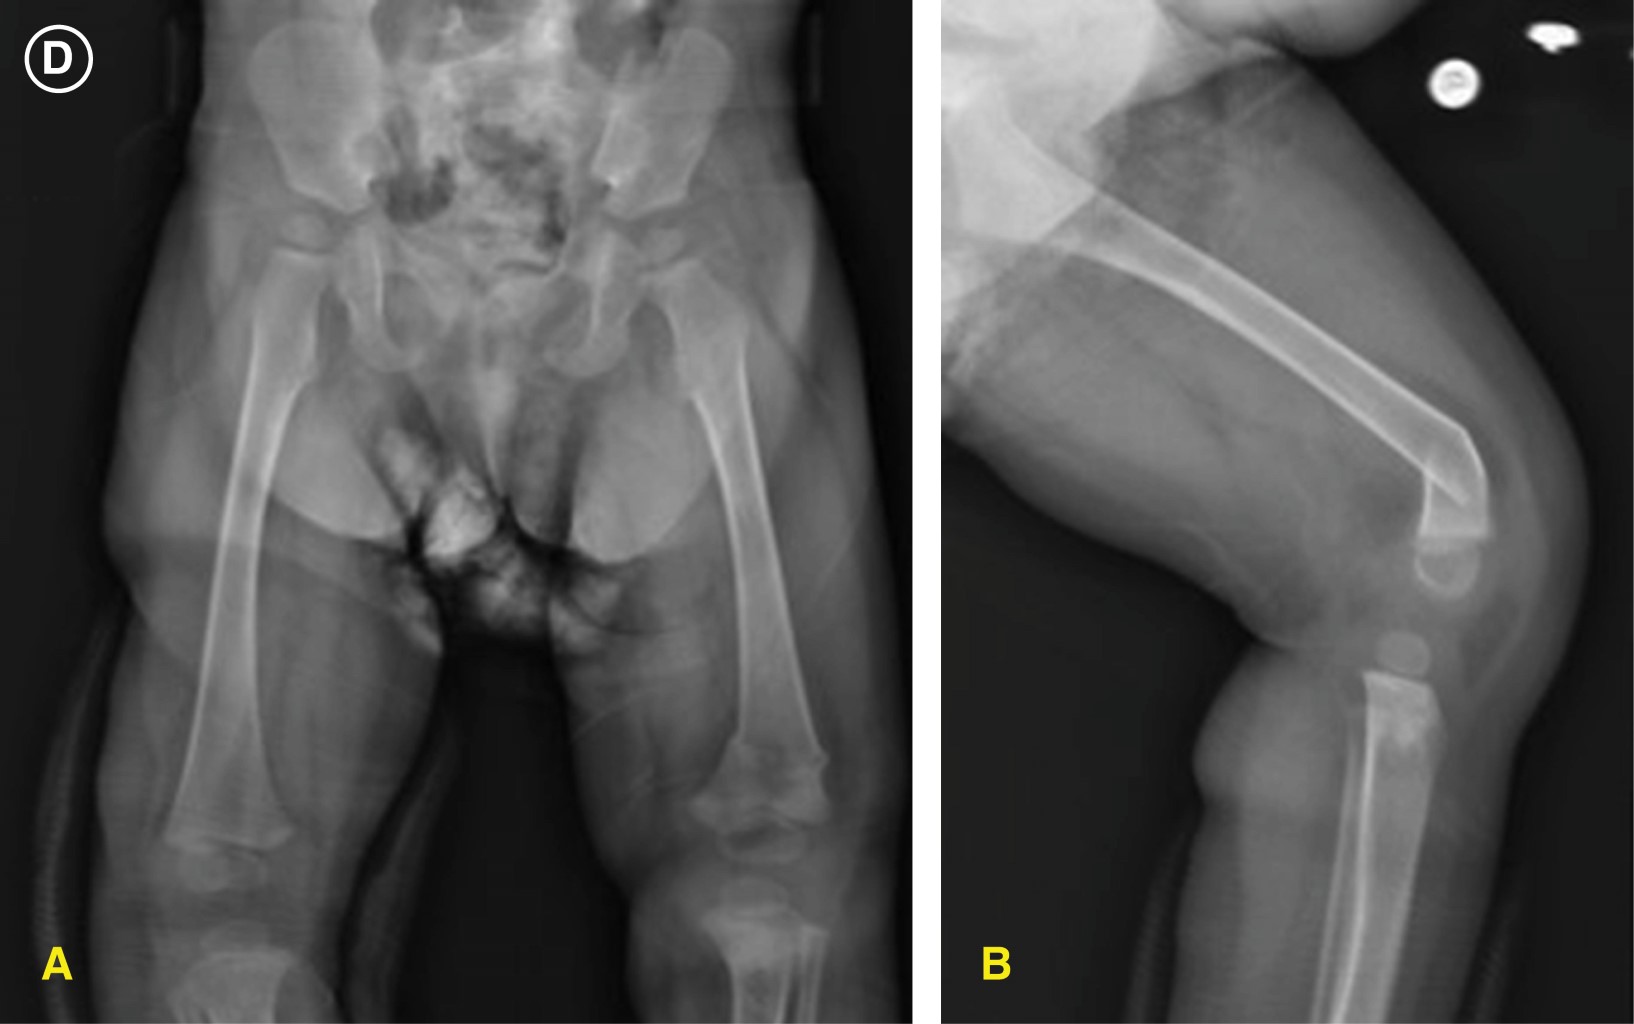

Multiple fractures caused by dystonia and muscular spasms in a patient with mitochondriopathy homozygous ECHS-1 gene mutation

Mitochondriopathies are rare genetic mutations of mitochondrial nuclear DNA that affect primarily the respiratory chain, decreasing the production of cellular ATP. These mutations can be de novo or congenital and have a broad spectrum of clinical presentations. They were first reported in 1958 and four to five new cases are reported per 100,000 births annually. They manifest more frequently as symptoms in organs with high energetic demand and are a diagnostic challenge due to the heterogeneity of clinical manifestations. We present the case of a 16-month-old patient with homozygous deletion mutation of ECHS-1 and glucose-6-phosphate dehydrogenase deficiency. ECHS-1 deficiency has been reported in less than 30 cases worldwide. The deletion manifests in the present case as psychomotor retardation, gastroesophageal reflux, dystonia of difficult control and muscle spasms that have twice caused traction fractures in metaphysis of long leg bones.

Figure 2